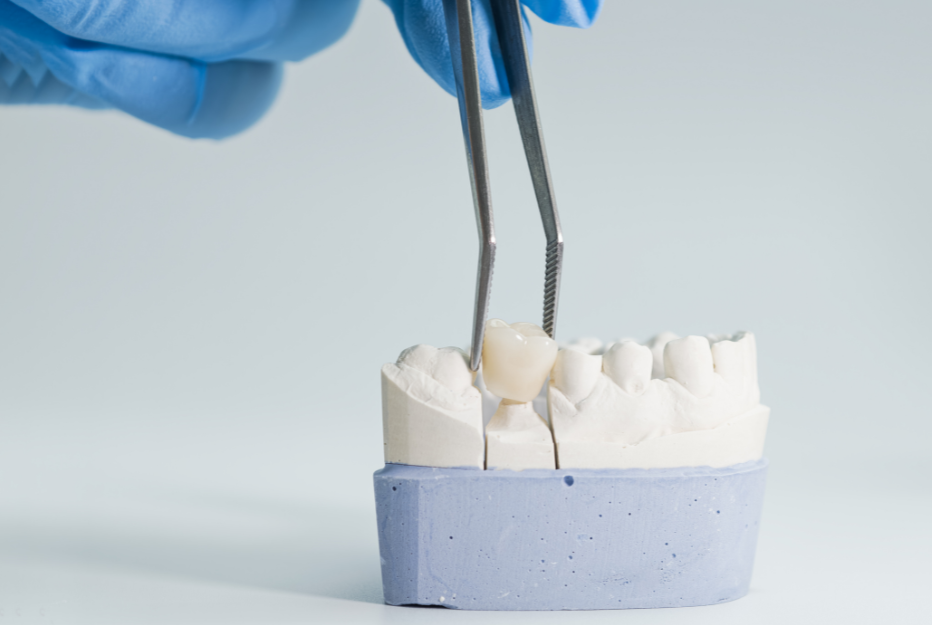

1. Dental Crowns and Inlays/Onlays

Years of grinding (bruxism) or acid erosion can wear down the enamel, making teeth shorter. This loss of height forces the jaw to close further than it should, putting pressure on the TMJ.

Dental crowns “rebuild” this lost height. By restoring the original shape and size of the tooth, we ensure the jaw closes in a neutral, relaxed position. Inlays and onlays provide a similar benefit for teeth that have less extensive damage.